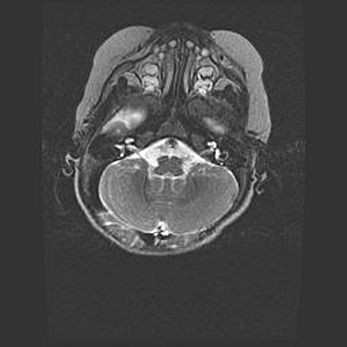

Подострая гематома правой гемисферы мозжечка.

Наружная гидроцефалия.

Возраст: 15 дней

Вес: 3100 г

Пол: женский

Окружность головы: 37 см

Срок гестации: 35-36 недель

При открытой наружной форме гидроцефалии у новорожденных расширяются и переполняются субарахноидные пространства.

Кровоизлияния в мозжечок имеют две клинико-анатомические формы: полушарные гематомы и кровоизлияния в червь.

К появлению этой патологии может привести: повреждения головного мозга, возникающие в результате асфиксии и гипоксии плода при беременности, или травмы во время родов. Редко гематома мозжечка может быть результатом первичной коагулопатии и сосудистой мальформации, диссеминированном внутрисосудистом свертывании, изоиммунной тромбоцитопении.